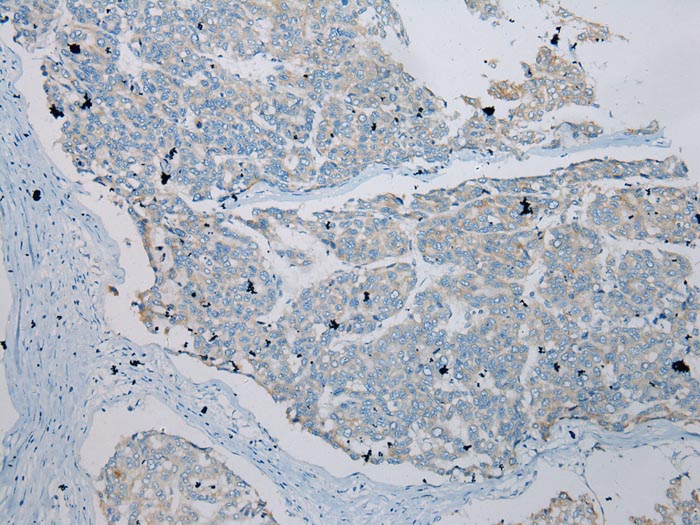

Immunohistochemical analysis of paraffin-embedded Human Liver cancer tissue using #43337 at dilution 1/100.